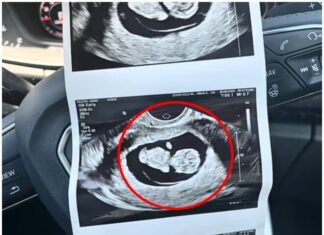

At her 20-week ultrasound, the expectant mother eagerly awaited the results, only to be met with a shocking revelation that left her reeling.